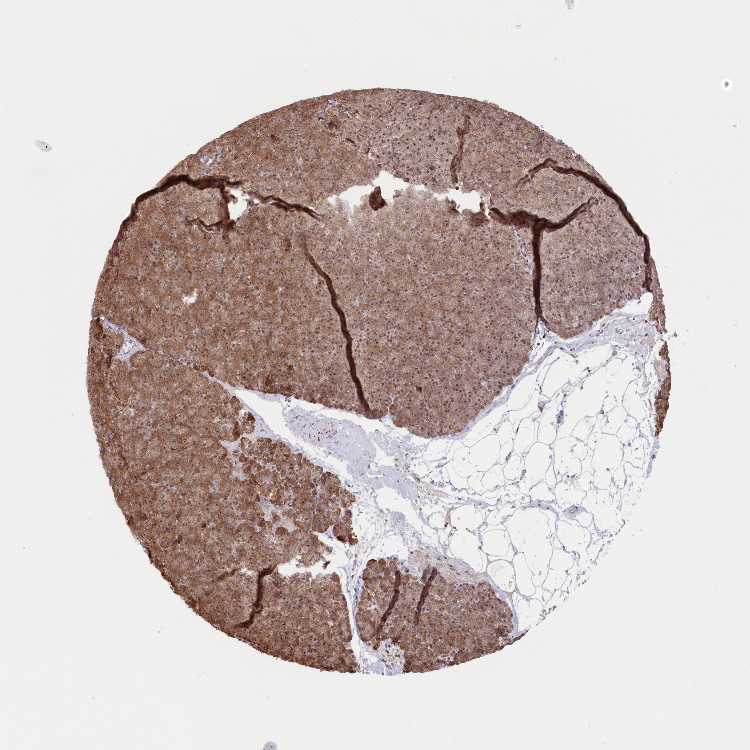

PANCREAS - Antibody stainingi

Antibody staining in the annotated cell types in the current human tissue is reported as not detected, low, medium, or high, based on conventional immunohistochemistry profiling in selected tissues. This score is based on the combination of the staining intensity and fraction of stained cells.

Each image is clickable and will lead to virtual microscopy that enables deeper exploration of all samples and also displays staining intensity scores, fraction scores and subcellular localization as well as patient and tissue information for each sample.

Antibody HPA035568Antibody HPA037017

Exocrine glandular cells MediumHigh

Pancreatic endocrine cells MediumHigh